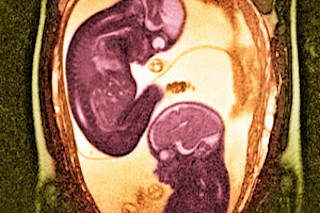

Humans are so social that newborn babies are able to imitate facial expressions of the people around them. In fact sociability begins even earlier, in the womb, according to Umberto Castiello and his team at the University of Padova. They used state-of-the-art ultrasound to monitor the movements of five pairs of fetal twins, between 14 and 18 weeks of gestation. The results, reported last October, show that even the youngest fetuses in the study recognized and responded to the other twin.

When reaching toward the co-twin—especially around the eyes and mouth—their motion was relatively slow and delicate. When the fetuses touched themselves, on the other hand, they were less cautious (although they approached their own eyes and mouth more gingerly than other parts of their body). They were roughest toward the uterine wall, kicking and shoving it with force. “In some very primitive form,” Castiello says, “it appears that the fetus by the second trimester already has a sense of ‘self’ that is different from ‘other.’ ”